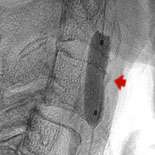

However, there are patients whose risk factors make surgery difficult. Such is the case with Ralph Waycott who was older and had lung problems which increase the risk for heart attack during general anesthesia. In addition, Ralph had radiation therapy in the neck which makes it difficult to operate due to the severe scarring. Ralph was symptomatic, having had 2 episodes of weakness of the right neck and showed narrowing of the left carotid artery.

The cutting edge treatment is to insert a carotid filter balloon which is an umbrella like device used to catch debris as the artery is being opened. Fig.1 shows Ralph's narrowing of the left carotid artery. Fig.2 shows the device being inserted in Ralph's artery. In fig.3 the carotid balloon's up showing inflation of the balloon which opens the blocked artery. A stent (fig.4) which is a metallic cage is placed in the artery to keep it opened.